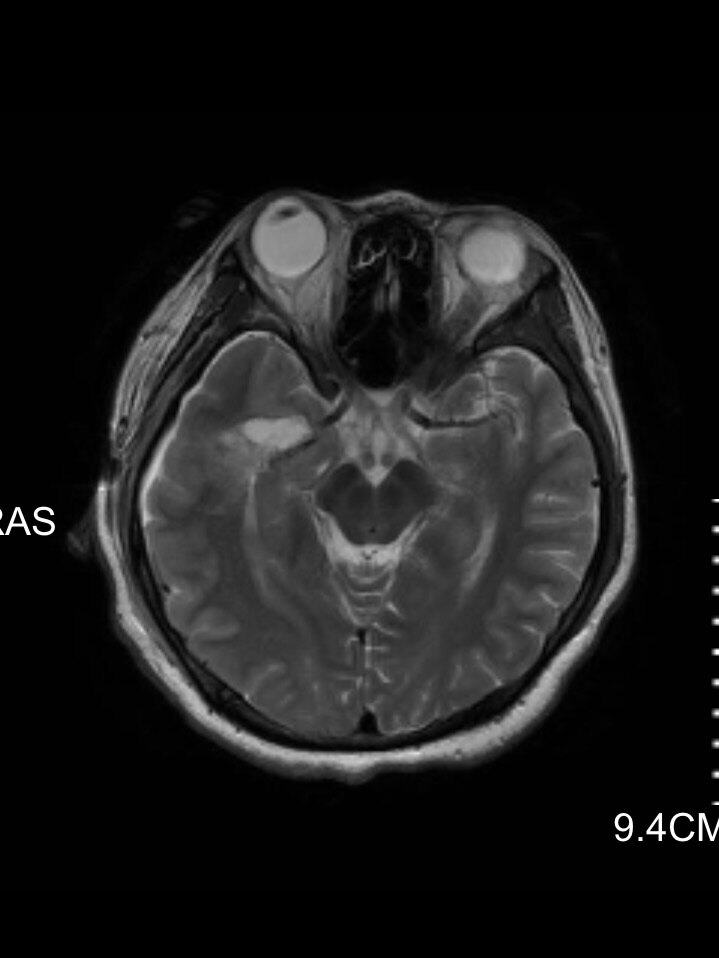

术后提示病变已切除

我们上周有一个24岁的花季女孩,因为突然晕倒发现颅内有一个海绵状血管瘤合并出血。很小的偶然发现的颅内的海绵状血管瘤如果没有症状,很多也可以暂时采取观察的措施就是定期复查头颅磁共振或者CT,不一定要马上手术治疗。但这个女孩发生了晕倒的症状,而且磁共振提示海绵状血管瘤有出血,所以还是强烈建议患者手术治疗。但这个女孩心理上无法接受理发,因为她的头发已经留了很多年,达到了“长发及腰”的水平,而且这个女孩从事舞蹈专业,对外貌要求非常高。所以我们跟女孩仔细沟通过后,没有理发,而是在手术切口上稍微剪掉了一点点头发,切口也是非常的微创,术后女孩恢复的也很快,没有发生感染的情况,术后4天非常满意的出院了。